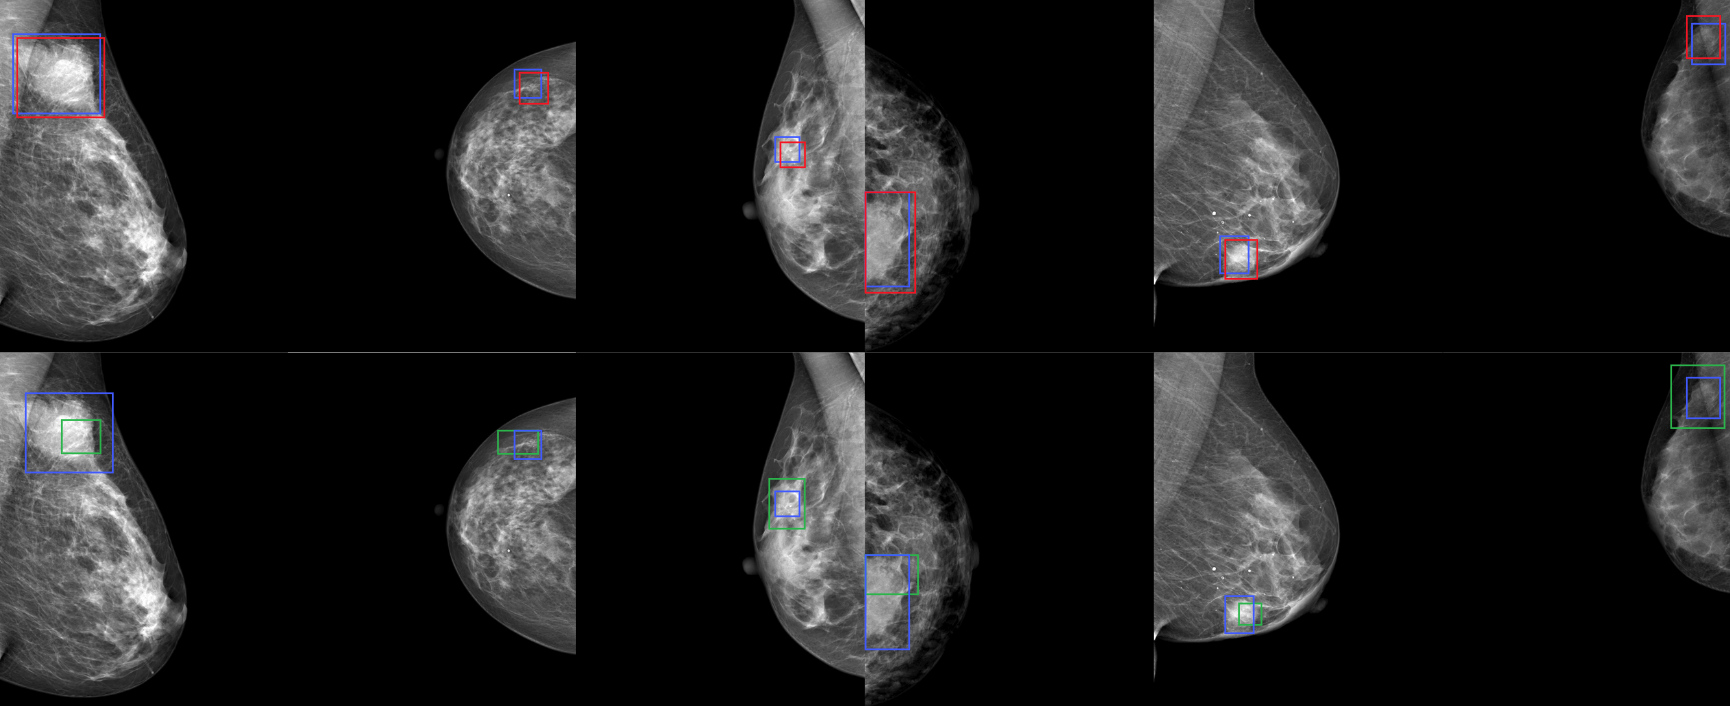

Refer to caption

Figure 4: Qualitative results of our proposed Grounded Teacher on Medical settings (DDSM \rightarrow INBreast). We present visual comparisons between AT (top row) and GT (bottom row). Our method, GT, effectively identifies Malignancies better and mitigates false negatives. Bounding box colors indicate: Blue — Ground truth, Green — true positive, and Red — false negative.